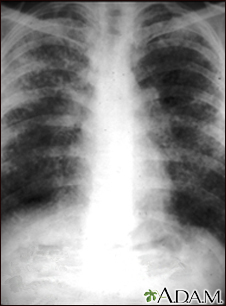

Sarcoid, stage II - chest x-ray